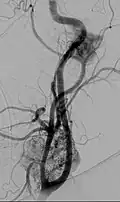

-

Micrograph of a carotid body tumor -

Digital subtraction arteriogram of carotid body tumor and jugular paraganglioma